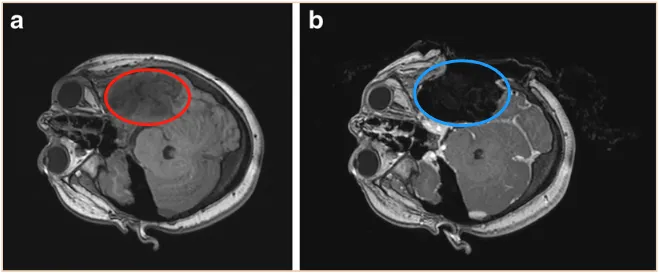

6岁女性患儿小乐因持续性头痛和反复癫痫发作,影像学检查发现左侧颞顶叶占位病变。肿瘤累及多个功能区且体积较大,手术风险高,首次手术仅实现部分切除。术后病理诊断为少突星形胶质细胞瘤(WHO 2级)。

5年后肿瘤复发,此时患儿11岁,需行二次手术。患儿家属转诊至德国国际神经科学研究所(INI),寻求Di Rocco教授治疗。二次手术全程采用术中神经电生理监测,在配备术中磁共振成像(iMRI)的手术室内通过导航引导完成肿瘤全切。术后3年随访观察未见肿瘤复发。

案例来源:Neurosurgical tools to extend tumor resection in pediatric hemispheric low-grade gliomas: iMRI